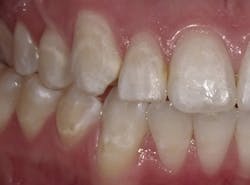

Figure 1 : Courtesy of Merrillville Family Dental Care in Merrillville, Ind.

I am not a full-time practicing hygienist. Thus, as a consultant, I selected one of my best offices and requested that they run a clinical trial that I monitored very closely. Dr. Chanbo Sim is a general dentist who is the owner of Merrillville Family Dental Care in Indiana. The clinical evidence from the trial included before-and-after pictures that were so astonishing that I wanted to share the evidence about this product with all of my offices throughout the United States.

It is important to understand two things about dental consulting in regard to products. Does the product offer real results that I can see with my own eyes, and is the product backed by research at the highest level? When I decide to test a product, I partner with client with whom I have built a long-term relationship. In this case, I chose Dr. Sim. They used Remin Pro on several patients, and I followed the patients from start to finish.

During the process, it is important that the office take a photo of the area of concern when talking about the problem and the consequence. This photo should ideally be taken by an intraoral camera and shared with the patient via computer, iPad, TV, or printed paper. During your explanation you should be able to share before-and-after photos (see Figure 1).